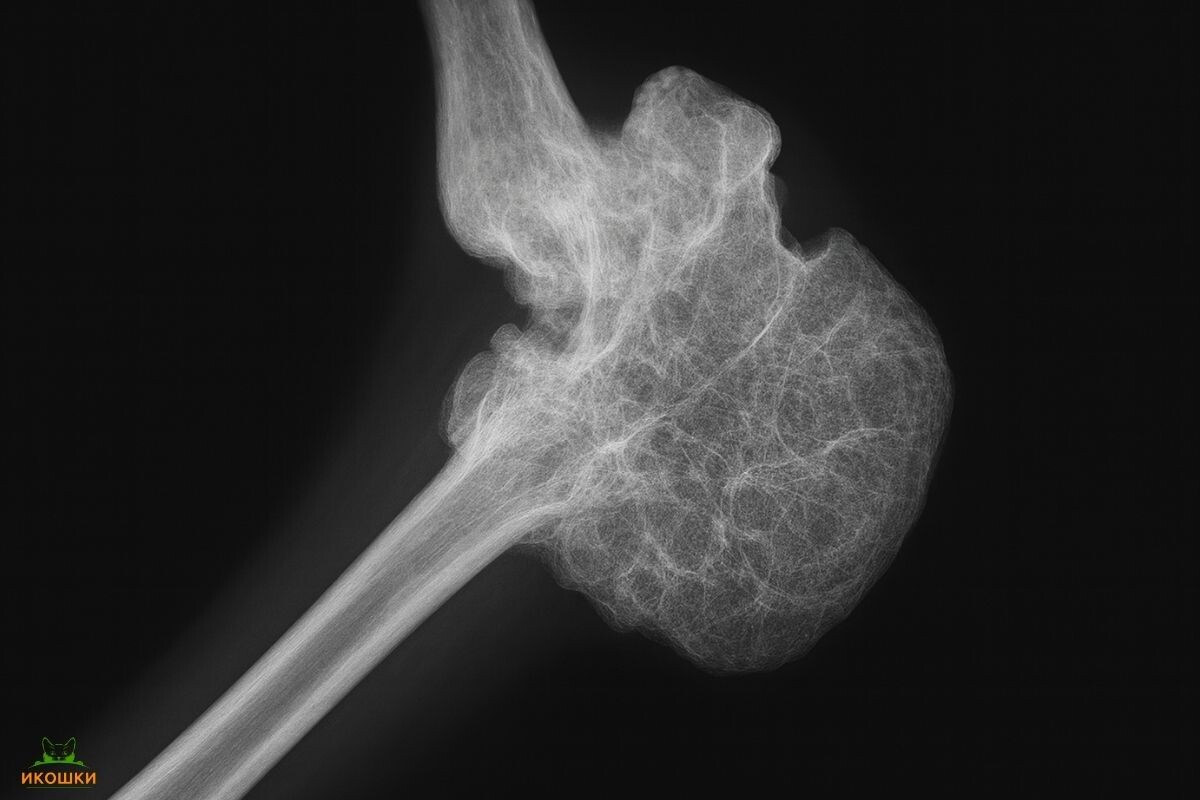

Поставить диагноз может только ветеринарный врач. Основным методом первой линии является рентгенография. На снимках специалист увидит характерные изменения: деформацию костей, костные разрастания (экзостозы) по краям суставов и сужение суставных щелей.

Изображение костных и хрящевых разрастаний при остеохондродисплазии